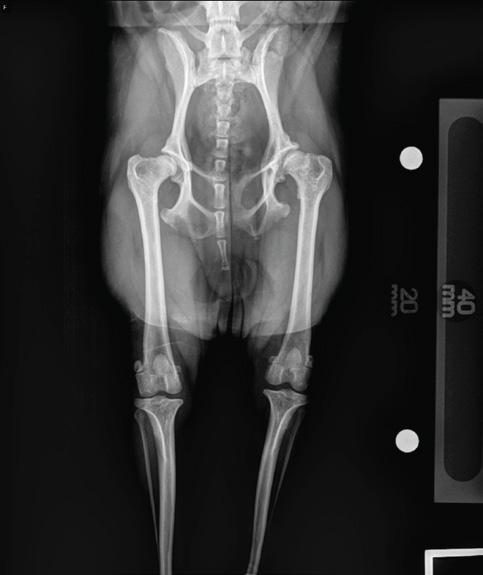

Diagnosis of hip dysplasia relies on clinical signs, radiographic evaluations, and consideration of the dog's age. Clinical signs may include rear leg pain, limping, a wobbly gait, and difficulty rising from a lying position. To make a definitive diagnosis, X-rays are necessary, typically requiring anesthesia for proper positioning. Common radiographic organizations such as the OFA and PENN Hip, are used to evaluate and screen the severity of hip dysplasia for pet owners and breeders.

Canine hip dysplasia (CHD) is a complex ailment characterized by the gradual destabilization of the hip joint due to structural abnormalities. While both genetic predisposition and environmental factors contribute to its development, the condition predominantly affects medium- to large-sized dog breeds, often leading to symptoms like hind limb lameness and muscular atrophy.

Radiographic imaging stands as the primary diagnostic modality, offering insights into bone changes associated with the disease. Notably, organizations like the Orthopedic Foundation for Animals (OFA) utilize extended hip projections to assess hip health in mature dogs, while alternatives like the PennHip method cater to younger patients.

Hip dysplasia is one of the most common skeletal disorders and causes of lameness in dogs. Many companion animals suffer from debilitating hip dysplasia, leading to hip subluxation with secondary osteoarthritis (see figure 1 and photo- pre and post-operative 2-year-old 2.8kg Brussels). Other causes of hip pain may be secondary to traumatic round ligament tear, hip luxation, osteonecrosis, or femoral head or neck fracture. Avascular necrosis of the femoral head and neck (Legg-Calve-Perthes disease) and slipped femoral capital epiphysis (SFCE) are conditions more prominent in small breed dogs and cats. Maine Coons and male, neutered cats have an increased predisposition for SFCE, with up to 36-41% of affected cats having bilateral disease.¹,²